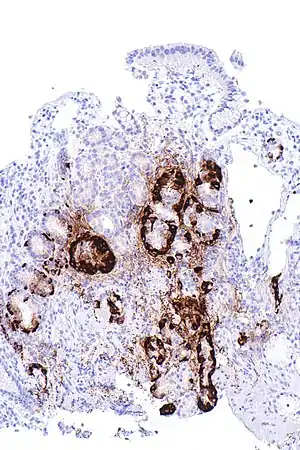

| Micrograph showing nodular enterochromaffin-like cell hyperplasia, as demonstrated with chromogranin A immunostaining, in the body of the stomach. Parietal cells are not readily apparent. These changes are in keeping with autoimmune metaplastic atrophic gastritis, a histologic correlate of Vitamin B12 deficiency anemia. | |